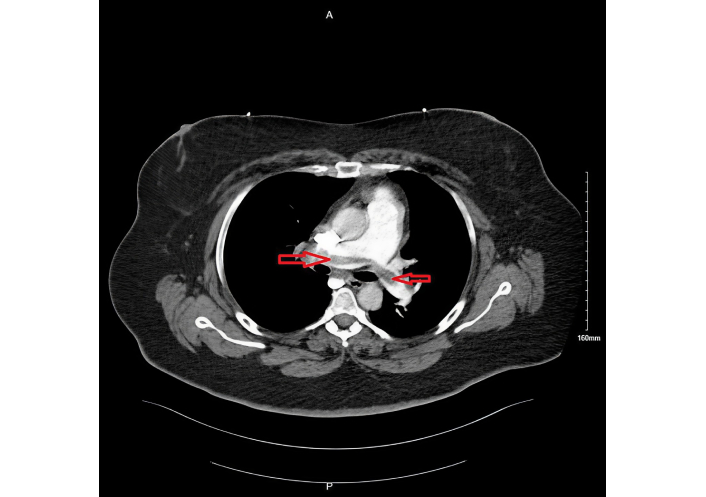

During her second hospitalization, pertinent laboratory findings included a pro-BNP of 3,554 pg/mL and troponin of 30 ng/L. Repeat CTA (Figure 2) again revealed persistent thrombus within the segmental and subsegmental pulmonary arteries, with right heart strain evidenced by right atrial and ventricular enlargement and an RV/LV ratio of 1.15. A limited echocardiogram demonstrated McConnell’s sign with dilated right-sided chambers, confirming ongoing right heart strain. Her PESI score was 90 points, corresponding to intermediate risk (Class III) with an estimated 30-day mortality risk of 3.2–7.1%, which guided the decision for further intervention.

Persistent pulmonary embolism during 2nd hospitalization, seen on computed tomography angiogram as filling defect (shown by red arrows).